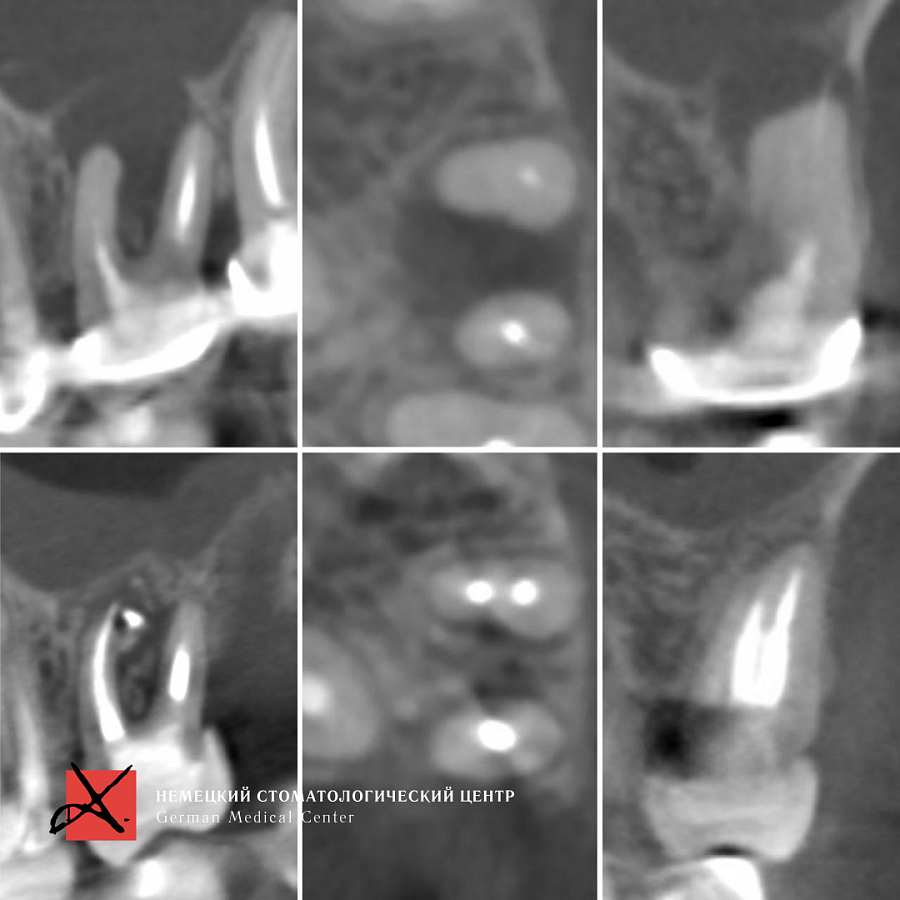

Этапы лечения

Лечение каналов под микроскопом